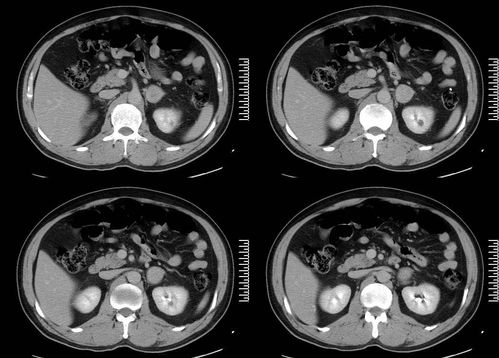

在临床实践中,血沉只能作为辅助指标,要联合肿瘤标志物、影像学(如CT/MRI)检查、病理活检等进行综合评估。例如,对于乳腺癌或结肠癌患者,如果血沉超过30mm/h,可能提示疾病进展,但也需要排除其他病因。